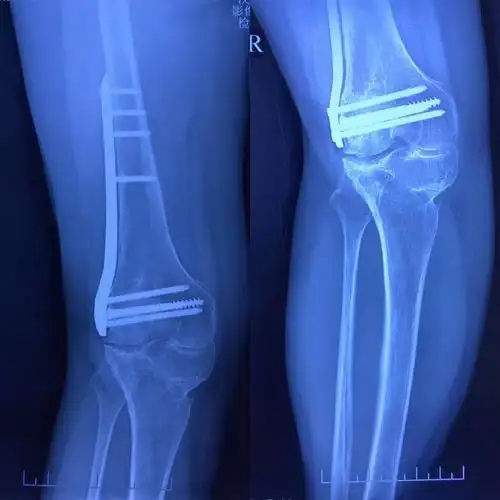

大荔县医院骨科——膝关节翻修为常规手术

援陕记实:一例右膝创伤性关节炎伴膝外翻的手术治疗探讨

双侧膝外翻病例分享

一例严重膝外翻合并骨关节炎患者行膝关节表面置换术

膝外翻病例1 - 好大夫在线

双膝外翻畸形tka牡林医骨六科张主任团队(副本)